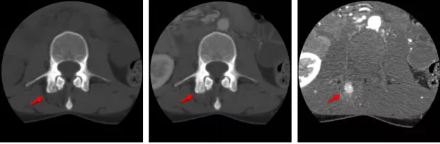

骨智能柔性減影成像功能發(fā)現(xiàn)隱匿骨占位病灶

相比傳統(tǒng)成像方式,肺部柔性減影技術(shù)通過人工智能,對平掃數(shù)據(jù)和CT肺動(dòng)脈血管掃描數(shù)據(jù)進(jìn)行智能比對,解碼并識(shí)別各個(gè)器官(肺、氣管、肺動(dòng)脈、肺靜脈、主動(dòng)脈等)的空間位置,并在三維空間中進(jìn)行體素級(jí)的柔性配準(zhǔn),從而極大提升了不同序列數(shù)據(jù)的空間位置的一致性。通過肺部柔性減影技術(shù)可得到肺強(qiáng)化碘圖,可以顯示出傳統(tǒng)CTPA圖像看不到的小栓塞病變,提高了栓塞檢出率,其結(jié)果甚至可與SPECT吻合。